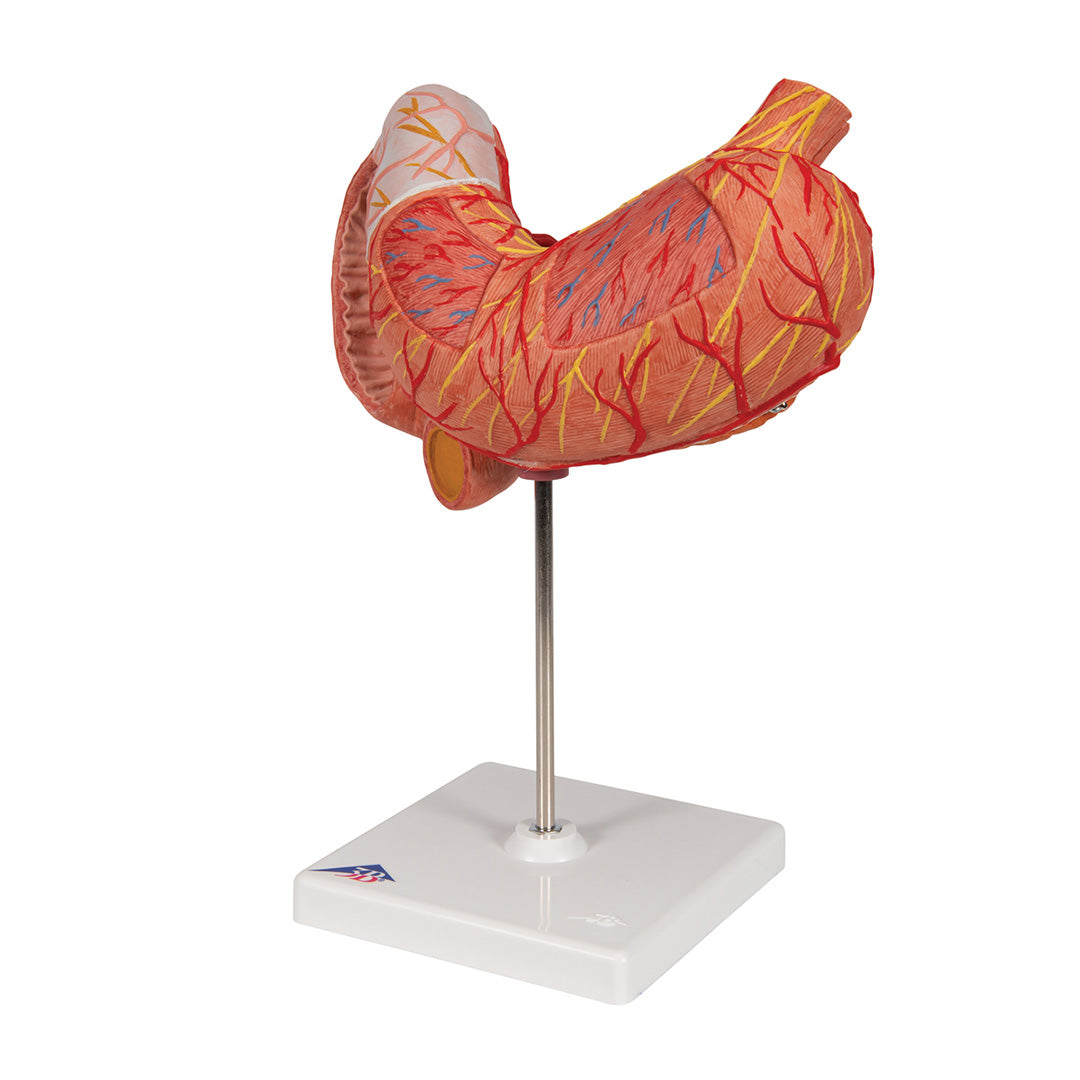

Estómago, en 3 piezas

Estómago, en 3 piezas

El modelo presenta las capas de la pared del estómago desde la cardia hasta el píloro.

La mitad delantera del estómago se puede retirar.

Se presentan:

• Parte inferior del esófago

• Conductos

• Nervios

• Duodeno

• Páncreas

Con soporte.

Peso 0.87 kg.

Dimension 25 x 22 x 12 cm